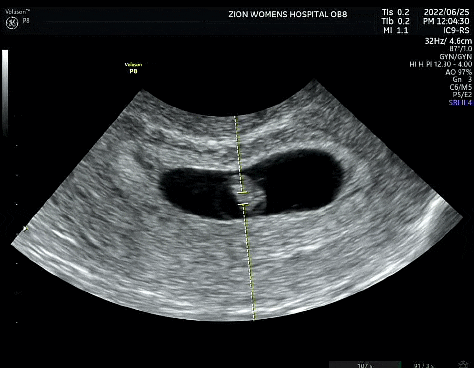

시온여성병원 간단후기

※ 지극히 주관적인 후기임을 미리 알려드립니다. ※ 제왕절개 수술 후기에서 못 다한 후기를 간단하게 적...

영통시온여성병원 제왕절개 후기[조산,임신중독]

육아 하느라 정신 없다보니 출산 후기가 많이 늦어졌네요.ㅠㅠ 올해 1월 갑작스런 임신중독으로 35주6일에 ...

임신주수별 검사 순서(1차 2차 기형아검사,태동검사,막달검사)

벌써 출산일이 다되가네요:) 저는 임신 하면서 궁금했었던 것 중 하나가 주수별 검사 였는데요 오늘은 제 ...